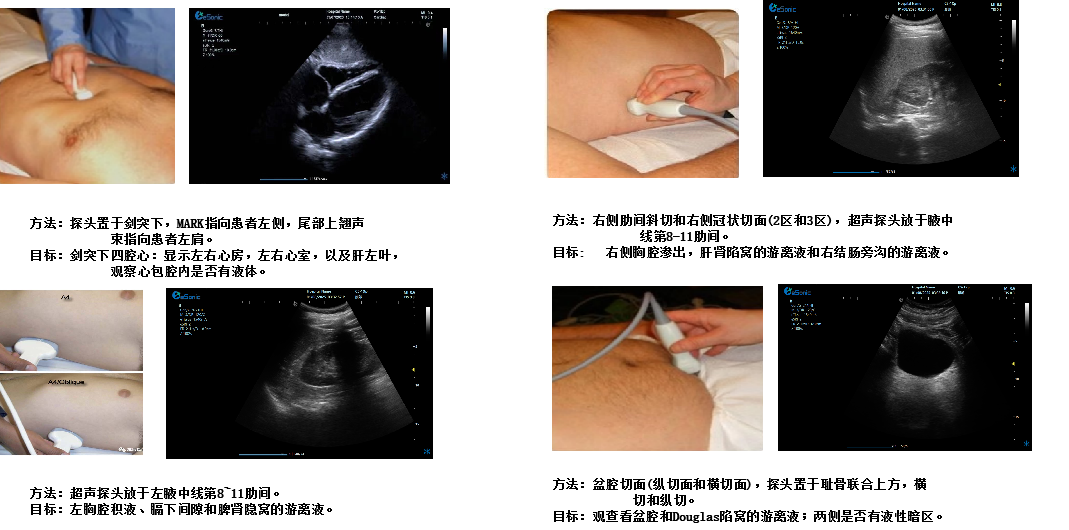

重症心脏超声- FATE方案:

是重症病人循环管理推荐的目标导向超声评估评估方案之一,在此基础上扩展快速的下腔静脉超声检查,增加和完善容量状态和液体反应性的评估。

胸骨旁左心室长轴切面image.png

扫查方法:探头放在胸骨左缘三到四肋间或距胸骨2-3cm处,探头标记指向患者右肩大约9-10点位置

超声声像图:显示左房、左室、主动脉、右室、室间隔及后壁;同时,此切面可观察二尖瓣及主动脉瓣的形态及运动。

胸骨旁大动脉短轴切面

扫查方法:探头置于胸骨旁第2、3肋间,在探查左室长轴切面基础上将探头顺钟向旋转90°

超声声像图:显示主动脉根部及三个瓣叶、左房、右房、三尖瓣、右室、右室流出道、肺动脉

胸骨旁左心室短轴切面(二尖瓣水平)

超声所见:左室呈圆形,右室呈新月形;舒张期二尖瓣前后叶开放呈“鱼口状 ”,收缩期关闭呈“”字形

胸骨旁左心室短轴切面(乳头肌水平)

超声所见:清晰显示前外、后内组乳头肌、室间隔、右心室、左心室及室壁,观察左心室壁中间段各节段运动情况

心尖四腔切面

扫查方法:探头放在心尖搏动处,使超声束由心尖向右上方指向心底。

超声声像图:显示左、右侧心房及心室、房室间隔;二、三尖瓣的形态及结构;心腔血流灌注、瓣膜返流等。

剑突下四腔心切面

image.png

扫查方法:探头置于剑突下,声束指向左肩,稍向上倾斜30°,接近心脏冠状切面

超声声像图:图像近场扇尖处可见肝实质反射,此切面可观察左心房、左心室、右心房、右心室、房间隔、室间隔、二尖瓣、三尖瓣等结构。

剑突下下腔静脉切面

扫查方法:在剑突下四腔心切面的基础上逆时针调整探头,直至标记指向被检者的头部,轻轻将探头向被检者右边倾斜。

超声声像图:显示右房,下腔静脉及肝静脉,注意观察下腔静脉及肝静脉有无扩张及搏动。

创伤评估FAST